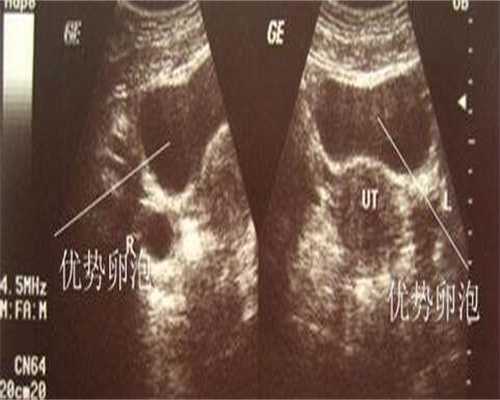

坤御宝虾青素复合片的功效有很多,每个人的体质不同,所以吃坤御宝所呈现的效果也会不同,综合来看备孕期吃坤御宝主要有以下作用效果:1. 坤御宝虾青素作为抗氧化剂服用,可以缓解卵巢功能退化,改善卵巢早衰的情况,自然备孕和试管助孕都可以服用;2. 增加基底窦卵泡数量,提高卵母细胞数量和卵母细胞质量,帮助提高受精卵质量,降低流产率,从而帮助成功怀孕;3、对于高龄对于高龄女性和自然受孕困难的女性,在备孕期间服用昆玉宝虾青素,可以提高胚胎质量,增加怀孕几率。昆玉宝复合虾青素片除了对备孕、助孕有很好的治疗效果外,本品还具有美容养颜、防止皮肤衰老的功效,虾青素可以防止皮肤受到紫外线的伤害。每个人的身体状况和需求不同,无论在哪种情况下使用坤御宝虾青素复合片,建议提前咨询专业人士。